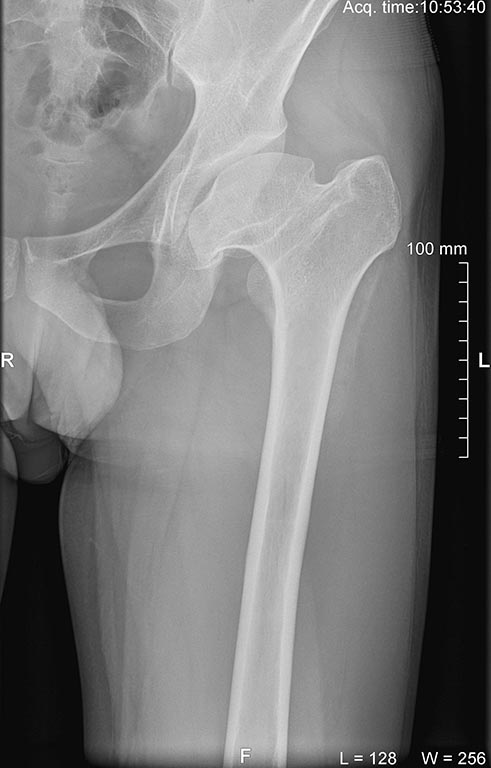

предоперационный снимок